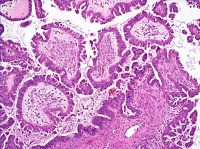

2、上皮性肿瘤:占卵巢肿瘤的50~70%,此中以浆液性肿瘤最常见,其次为粘液性肿瘤。以其构造学及细胞学特点,它们各有良性、交界性(低度潜伏恶性瘤)及恶性之分。上皮腺瘤占卵巢恶性肿瘤的90%。

卵巢肿瘤可以是良性的、良恶性交界及恶性的肿瘤,其病理形态多种多样,根据卵巢的组织发生来分类,可分为:(1)生发上皮肿瘤 约占全部肿瘤的40%,有浆液性和粘液性及混合性上皮生发肿瘤,恶变率较高。(2)生殖细胞瘤 来自生殖细胞及其衍生组织,包括无性细胞瘤、畸胎瘤、内胚窦瘤、绒毛膜上皮癌等肿瘤。(3)性索间质肿瘤 约占卵巢肿瘤的6%,该类肿瘤较为复杂,各种细胞可单独组成相应的肿瘤,卵巢型或睾丸型的两种细胞可出现在同一肿瘤内,更有4种细胞类型同时在肿瘤内见到。(4)类固醇细胞瘤 类固醉细胞瘤由类似于黄体细胞、间质细胞、肾上腺皮质细胞的大圆形或大多边形细胞组成。以往称脂质细胞瘤或类脂细胞瘤。

1.良性,囊腺瘤和乳头状囊腺瘤,表面乳头状瘤,腺纤维瘤和囊腺纤维瘤。

2.临界恶性(低度恶性潜能) 囊腺瘤和乳头状囊腺瘤,表面乳头状瘤,腺纤维瘤和囊腺纤维瘤。

3.恶性腺癌、乳头状腺癌和乳头状囊腺癌,表面乳头状腺癌,腺癌纤维瘤和囊腺癌纤维瘤。